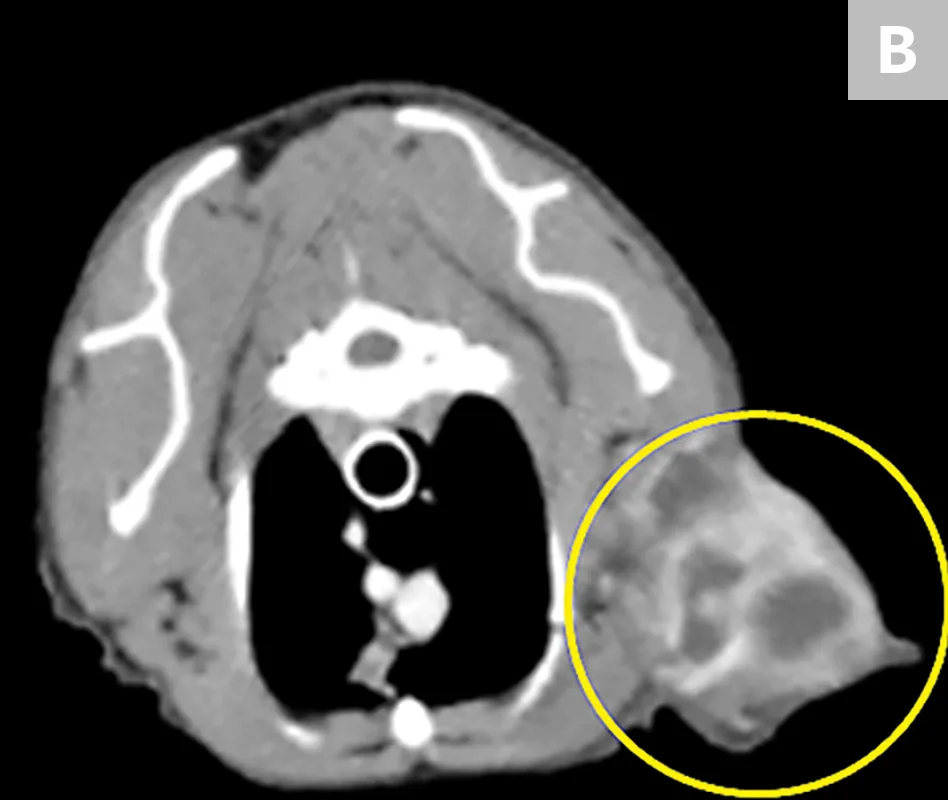

This prospective study examined the agreement between the measurement (length and width) of ISS sizes when assessed by digital calipers (clinical method) and contrast-enhanced CT (Figure). Over a span of 11 years at a single institute, the tumor dimensions of 53 pet cats with ISSs were evaluated before surgery by a single surgeon using the clinical method and by a single radiologist using the CT method.

Clinical measurement with manual calipers (A) of an ISS involving the soft tissues overlying the right distal lateral humeral region of a cat. A transverse view with contrast-enhancing CT (B) in the same patient readily identifies a multilobulated soft tissue tumor (yellow circle) with discrete regions of peripherally enhanced vascular growth and proliferative tumor tissues.

Caliper and CT methods tended to be in agreement directionally; however, CT methods consistently estimated greater tumor sizes (length and width) as compared with the clinical method. The agreement between clinical and CT methods became more divergent as a function of increasing tumor size. In addition, the characterization of ISSs as adopting irregular-shaped growth patterns (vs spheroid or ovoid) was identified more readily by CT methods.